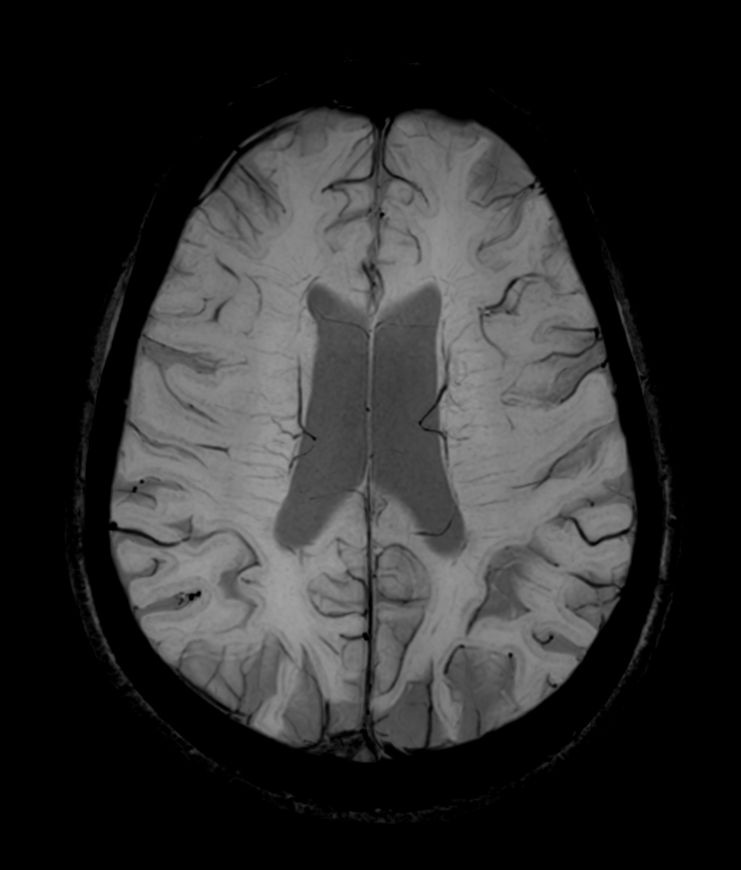

T2w TSE MultiVane XD